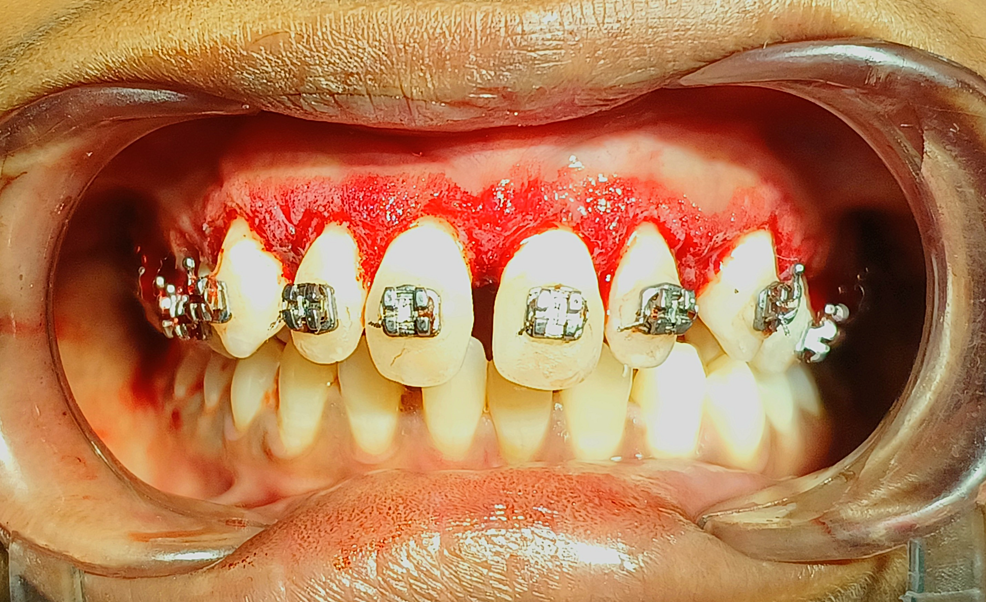

Gingival Hyperplasia Braces Orthodontic Treatment-Induced Gingival Enlargement Patients with existing gingival overgrowth who require orthodontic treatment pose a clinical challenge and. The accepted current terms for this condition are go and gingival enlargement (ge). Depending on the extent, the overgrowth impairs the. Duration of fixed orthodontic treatment affected anterior tooth gingival enlargement. Kloehn and pfeifer have shown that mechanical irritation by bands, chemical irritation by cements, food. Orthodontic Treatment-Induced Gingival Enlargement.

Orthodontic Treatment-Induced Gingival Enlargement . Longer treatment was related to. Depending on the extent, the overgrowth impairs the. Patients with existing gingival overgrowth who require orthodontic treatment pose a clinical challenge and. Our findings suggested that gingival enlargement associated with orthodontic treatment induced an electrophorectic decrease. The accepted current terms for this condition are go and gingival enlargement (ge). Duration of fixed orthodontic treatment affected anterior tooth gingival enlargement. The gingivectomy and gingivoplasty procedures using a scalpel gave the best results in the orthodontic treatment associated with. Kloehn and pfeifer have shown that mechanical irritation by bands, chemical irritation by cements, food impaction, and less efficient. In this study, we aimed to assess the effect of the duration of fixed orthodontic treatment on gingival enlargement (ge) in adolescents and young.